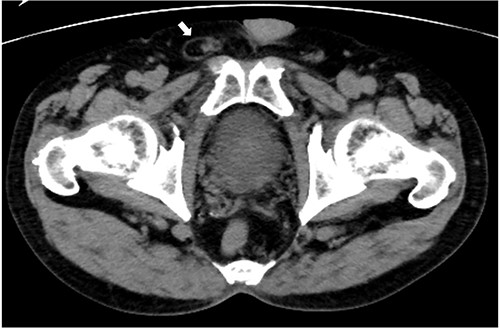

A 75-year-old man with a history of adult Still’s disease for over 10 years was referred to our hospital owing to a right inguinal pain. The patient had been receiving tocilizumab (8 mg/kg, every 2 weeks) and prednisolone (4 mg daily). Abdominal computed tomography revealed a groin hernia in the right inguinal region (Fig. 1). The patient was diagnosed with a right inguinal hernia, and surgery was scheduled. Tocilizumab was discontinued 3 weeks before the surgery. The low dose of prednisolone (4 mg) was continued, and no steroid coverage was performed before or after the surgery.

Abdominal computed tomography imaging. A groin hernia in the right inguinal region (arrow).